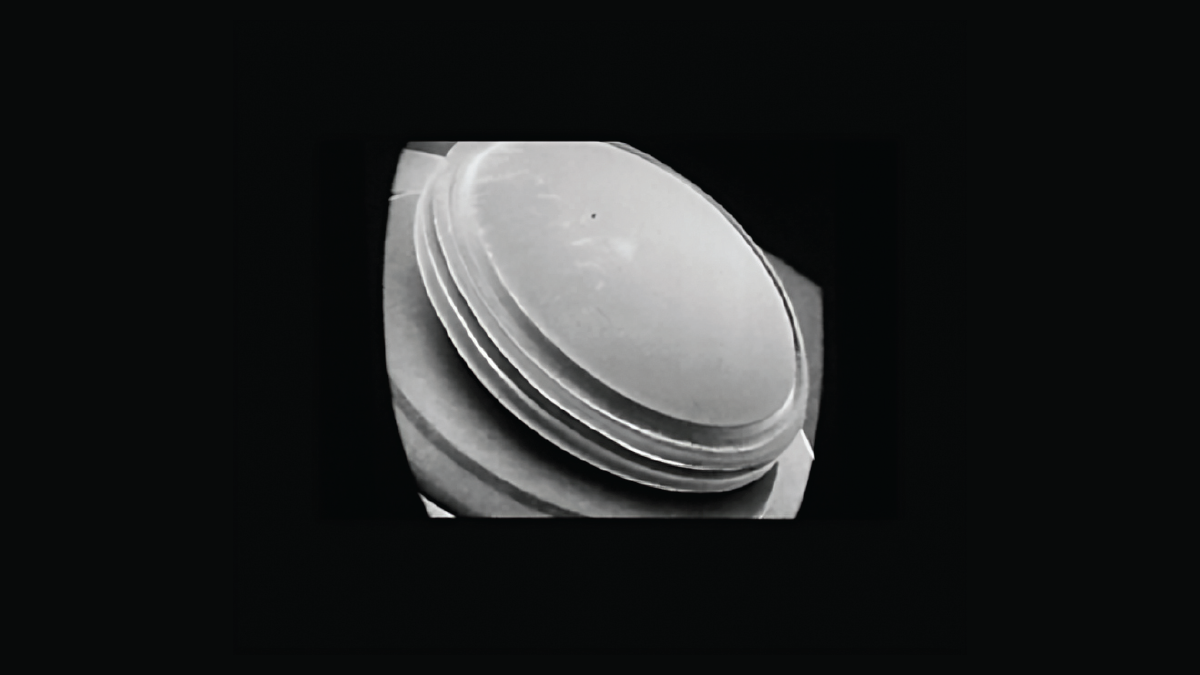

British ophthalmologist Harold Ridley (1906-2001) pioneered a new era in ophthalmology when he implanted his first intraocular lens (IOL, Figure 1). The story is well known, but new research based on records of the period throws some new light on this historic event (1).

Ridley performed an extracapsular cataract extraction on a 45-year-old woman on November 29, 1949, placing a Perspex lens in the patient’s eye. However, according to his resident, Peter Choyce, Ridley immediately removed the lens, because he lacked confidence that the lens had adequate stability (1). It had no haptics to provide stability; the lens also resulted in a myopic outcome of -21 diopters and the cetrimide sterilization could be associated with uveitis. Thus, the IOL required additional modifications before it could be accepted. On February 8, 1950, Ridley re-implanted the IOL in the same patient.